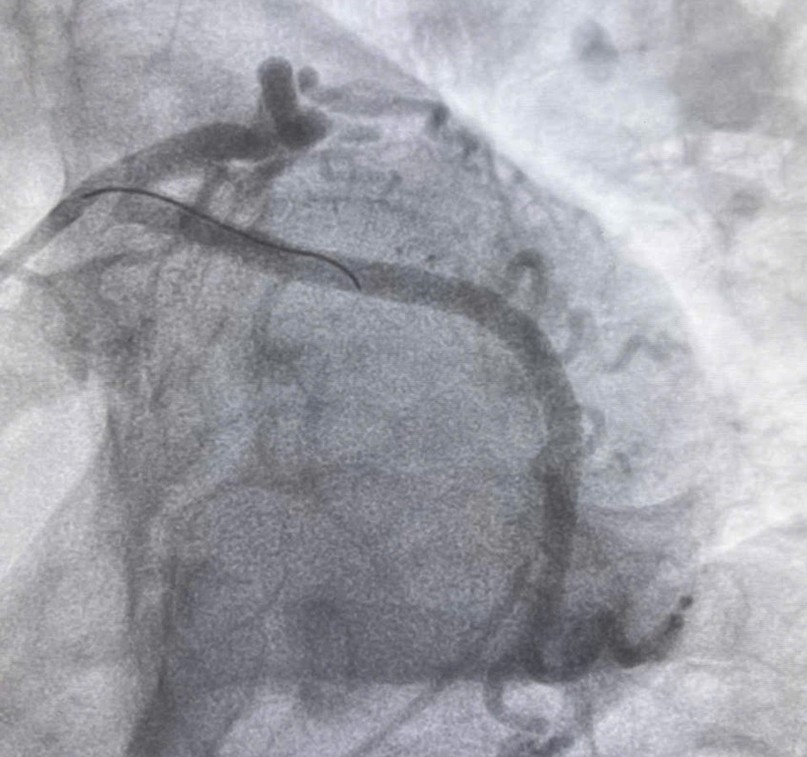

Hình ảnh động mạch vành của bệnh nhân sau đặt stent.

Bác sĩ Khoa Cấp cứu chống độc đã liên hệ hội chẩn Khoa Nội tim mạch, kết luận bệnh nhân bị nhồi máu cơ tim cấp vùng sau dưới và được chụp động mạch vành cấp cứu. Kết quả cho thấy bệnh nhân hẹp khít kèm huyết khối động mạch mũ (1 trong 3 nhánh động mạch vành) nên dẫn tới nhồi máu cơ tim vùng sau dưới. Sau khi đặt stent cho bệnh nhân, động mạch mũ được thông tốt. Sau 4 ngày điều trị, bệnh nhân đã tỉnh táo, huyết động ổn định, tình trạng đau ngực không còn, có thể xuất viện trong vài ngày tới.